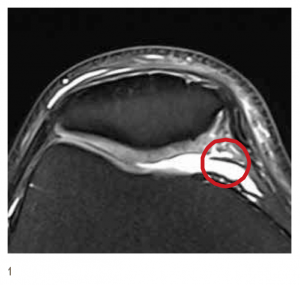

Mit der Magnetresonanztomographie (Kernspin, MRT) als sehr sensiblem bildgebenden Verfahren lässt sich eine Plica sicher darstellen. Es müssen allerdings die richtigen Sequenzen verwendet werden und dem Untersucher muss das Krankheitsbild vertraut sein. Daher ist die Diagnose eines Plicasyndroms meist eine klinische Diagnose in der Hand eines erfahrenen Unfallchirurgen oder Orthopäden oder aber ein Zufallsbefund bei einer Kniegelenksspiegelung (Arthroskopie) aus anderem Anlass.